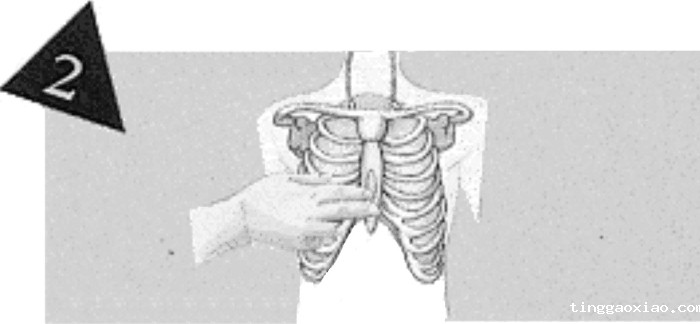

将中指置于心窝处,食指紧靠中指,置于胸骨上定位。

将另一掌的掌根紧靠在已定位的食指旁,使掌根的位置正好放在胸骨的中线上。